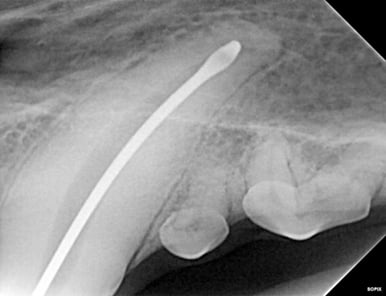

Below: Radiograph of 204 of the apex (tip of root). Beyond the wide pulp chamber, nothing significant is noted, yet studies show 43% of discolored teeth have no radiographic signs of problems, but have pulp necrosis and disease that leads to additional, potentially systemic issues.

%20-%20March%202024/Radiograph%20before%20RCT%20-%20apex.jpg?width=386&height=297&name=Radiograph%20before%20RCT%20-%20apex.jpg)

Below: Before RCT - Radiograph of 204 to aid in planning the access point

%20-%20March%202024/radiograph%20before%20RCT%20-%20access%20point.jpg?width=386&height=297&name=radiograph%20before%20RCT%20-%20access%20point.jpg)

A root canal procedure was performed on tooth 204, which was non-vital. To access the pulp chamber, a round surgical length bur was utilized. Upon reaching the pulp chamber, a radiograph was taken to ensure cleaning at the working length, which in this case was 38mm. Cleaning and shaping of the canal were carried out using Dentsply NiTi and LightSpeed files in alternation with suction aided sterile saline and sodium hypochlorite solutions.

Below: During RCT - Radiograph finding working length to clean and measure canal

%20-%20March%202024/during%20RCT%20-%20finding%20working%20length.jpg?width=379&height=291&name=during%20RCT%20-%20finding%20working%20length.jpg)

Below: During RCT - finding master file size to clean canal walls appropriately and find master cone size of gutta percha

%20-%20March%202024/Radiograph%20of%20master%20file%20during%20RCT.jpg?width=386&height=296&name=Radiograph%20of%20master%20file%20during%20RCT.jpg)